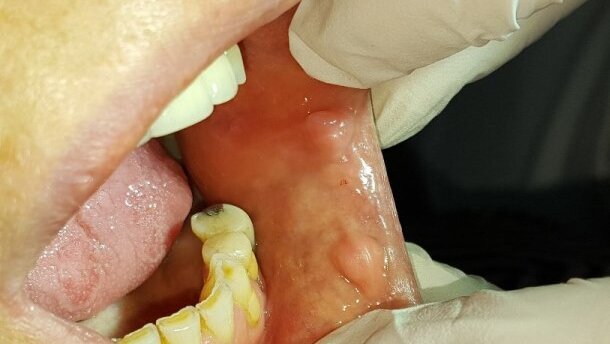

57-letnia pacjentka zgłosiła się do Zakładu Chirurgii Stomatologicznej w celu przygotowania pola protetycznego do ponownego protezownia. Pacjentka użytkowała protezę całkowitą dolną i górną. W badaniu podmiotowym nie stwierdzono odchyleń. W badaniu przedmiotowym wewnątrzustnym stwierdzono duży zanik wyrostka zębodołowego żuchwy, a na błonie śluzowej zmiany włóknisto-przerostowe o charakterze fałdów włóknistych, wynikające z długotrwałego użytkowania niedopasowanego uzupełnienia protetycznego oraz zmianę o charakterze brodawczaka.

59-lernia pacjentka zgłosiła się do Zakładu Chirurgii Stomatologicznej WUM w celu leczenia zmian na błonie śluzowej jamy ustnej. W badaniu podmiotowym nie stwierdzono odchyleń. Pacjentka podaje pojawienie się zmian ok. 10 lat temu oraz zgłasza nawykowe nagryzanie błony śluzowej policzków.

W badaniu przedmiotowym wewnątrzustnym stwierdzono liczne braki zębowe, ostre krawędzie zębów, mnogie zmiany na błonie śluzowej policzków i kątów warg o charakterze włóknisto-przerostowym (fibroma), zmiany o średnicy 0,7-1,0 cm. Pacjentce zaproponowano usunięcie zmian za pomocą lasera CO2. Pacjentka wyraziła zgodę na zabieg.